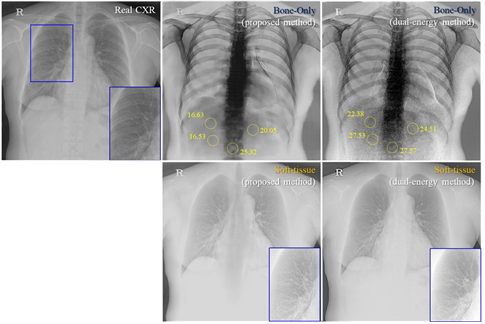

Results: Our results indicate that the proposed framework is effective and exhibits potential synthetic imaging ability for two relevant materials: soft tissue and bone structures. Its effectiveness was validated, and its ability to overcome the limitations associated with DE imaging techniques (e.g., increase in exposure dose owing to the requirement of two acquisitions, and emphasis on noise characteristics) via an artificial intelligence technique was presented.

- 최근 연구에서는 기존의 이중 에너지(Dual-energy, DE) 흉부 방사선 촬영(CXR)을 대체할 새로운 프레임워크 개발에 주목하고 있습니다. 이 기술은 연조직과 뼈 구조를 선택적으로 영상화하여 다양한 흉부 병리(예: 폐 결절, 뼈 병변 등)를 더 정확하게 특성화하고, CXR 기반 진단의 개선 가능성을 모색합니다. 특히, 이번 연구는 단일 에너지 컴퓨터 단층촬영(CT)에서 DE와 유사한 CXR 영상 합성을 위한 새로운 프레임워크를 개발하는 것을 목표로 합니다. 이를 위해, AI 기반으로 한 프레임워크가 제안되었습니다. 제안된 프레임워크는 가상 CXR 생성부터 실제 단일 에너지 CXR에 대한 학습 및 추론까지, 세 가지 주요 기술로 구분됩니다. 연구 결과는 제안된 프레임워크가 소프트웨어 기반의 뼈 전용 및 뼈 억제 이미지를 CXR에서 유용하게 사용할 수 있는 대안으로서의 가능성을 보여줍니다. 이 연구는 특히 방사선 영상 분야에서 X-선의 선량 문제를 해결하고, 단일 노출로 가상 DE 영상을 가능하게 하는 새로운 방법론을 제시함으로써 의료 영상 진단의 질을 향상시킬 수 있는 유망한 접근 방식을 제시합니다.